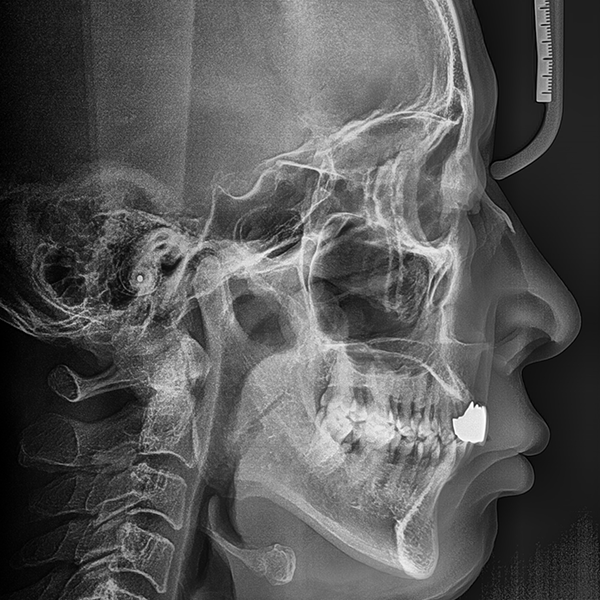

3. 症例.153 60代 イ*ゲ 2020-01-19 / 2020-1-20

上顎/前歯部 / 4本以上 / 骨移植|高血圧

症例.153 60代 イ*ゲ 2020-01-19 / 2020-1-20